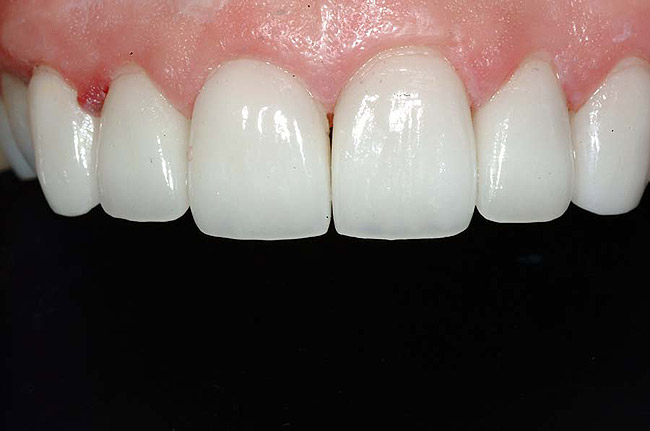

Figure 1 and Figure 2 Preoperative views of a female patient in her mid-50s who presented with a chief complaint of dissatisfaction with the appearance of her smile. Examination revealed multiple fractures, hypocalcification, shortened clinical teeth due to wear, and an asymmetrical smile line. Teeth Nos. 6 through 11 were treatment planned for porcelain laminate veneers.

In fact, scientists evaluating the long-term functionality of porcelain laminate veneers after 1 to 10 years of service observed that they had been placed for such reasons as correcting fractured and worn anterior teeth, treating surface enamel defects, and changing the appearance of intrinsically discolored dentition (Figure 2');" rem="#ip:figure1 and Figure 2">Figure 1 and Figure 2).2 These researchers found that the porcelain laminate veneer concept provided excellent esthetic and conservative restorations. In other studies, researchers observed 5-year success rates with porcelain laminate veneers,3 commenting that they offer a reliable and effective procedure for the conservative and esthetic treatment of anterior dentition.